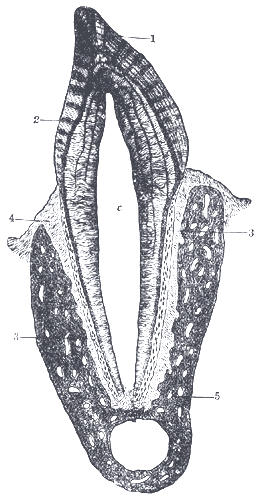

| Vertical section of a tooth in situ | |

c: the pulp cavity, opposite the neck of the tooth; the part above it is the crown, that below is the root.

1. Enamel with radial and concentric markings. 2. Dentin with tubules and incremental lines. 3. Cement, with bone corpuscles. 4. Periodontal membrane. 5. Mandible. |

Public domain: 20th U.S. edition - Gray's Anatomy of the Human Body, 1918 |